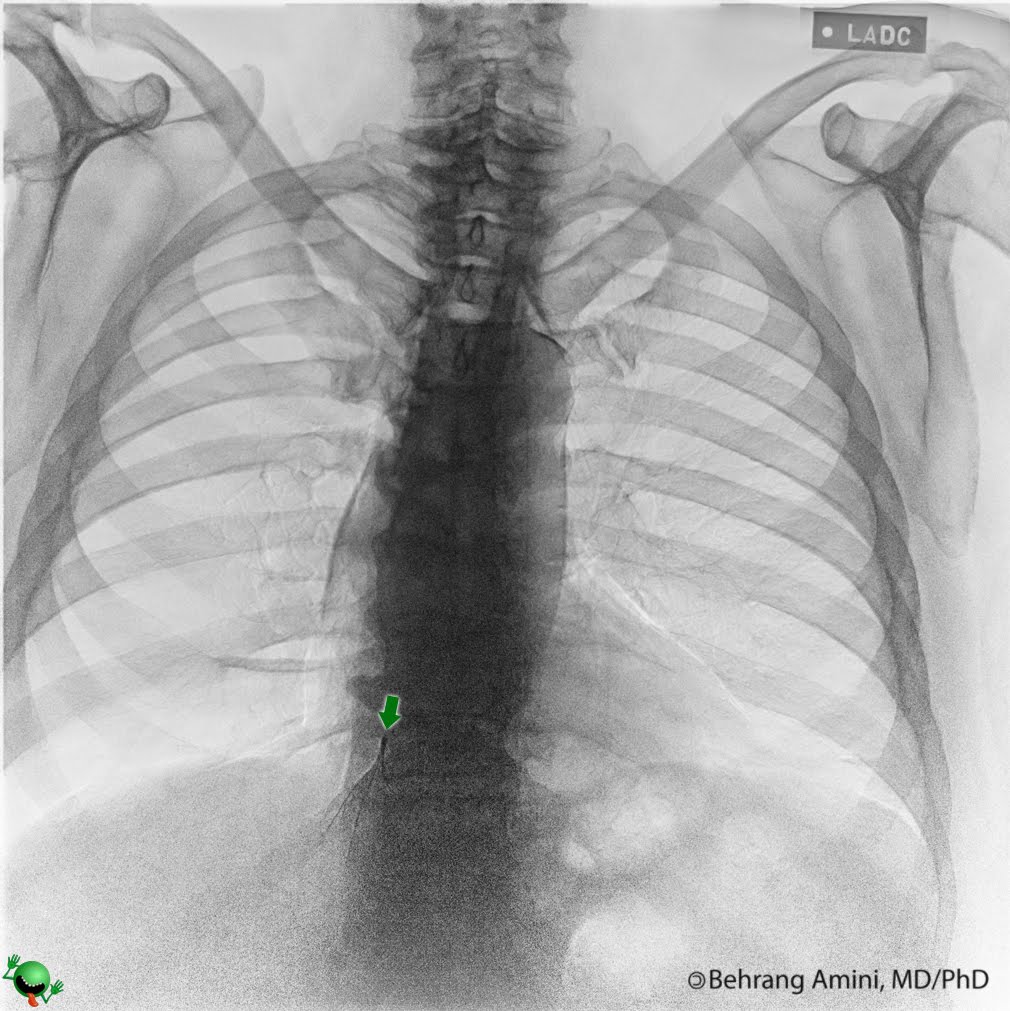

Ivc Filter X Ray Image . identification of permanent and retrievable ivc filters and individual filter types on diagnostic imaging is important. ivc filter strut penetration at ct. inferior vena cava filters (ivc filters) are indicated as a treatment.

inferior vena cava filters (ivc filters) are indicated as a treatment. identification of permanent and retrievable ivc filters and individual filter types on diagnostic imaging is important. ivc filter strut penetration at ct.

Ivc Filter X Ray Image ivc filter strut penetration at ct. ivc filter strut penetration at ct. identification of permanent and retrievable ivc filters and individual filter types on diagnostic imaging is important. inferior vena cava filters (ivc filters) are indicated as a treatment.